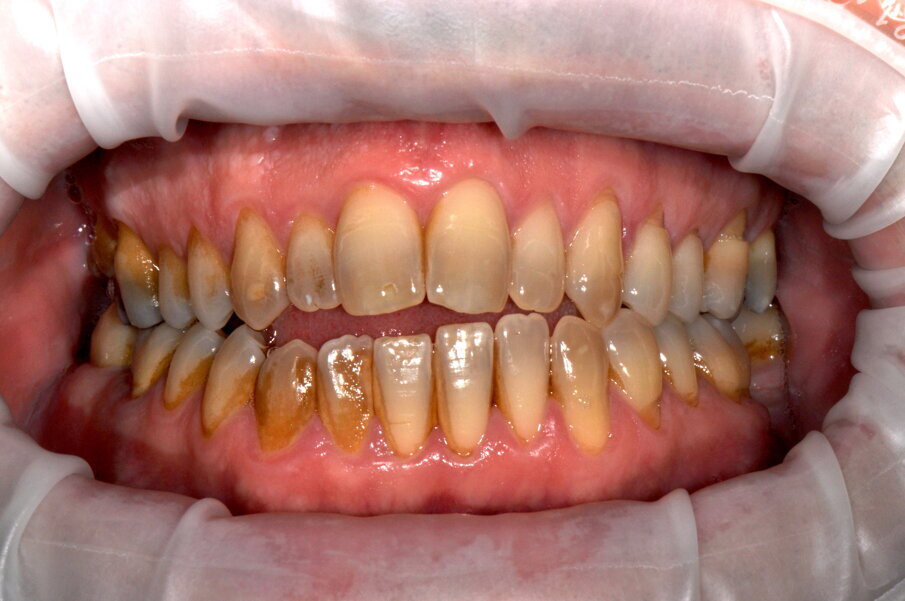

GianPietro, 50 anni, si presenta per la seduta di igiene professionale dopo un anno dall’ultimo richiamo. Si presenta con depositi di placca e tartaro diffusi e lieve gengivite generalizzata da placca. Già dopo la seduta di GBT la differenza di colore è evidente, ma il paziente chiede se si può fare di più. Si propone perciò lo sbiancamento professionale con perossido d’idrogeno al 6% seguito da domiciliare con mascherina e perossido di carbammide al 17% per ottenere il massimo del risultato nel tempo e verificare la compliance domiciliare del paziente.

Fig. 6 - Fotografia frontale scattata prima della seduta di igiene orale professionale (Guided Biofilm Therapy).

Fig. 7 - Fotografia frontale scattata dopo la seduta di igiene professionale mediante l’utilizzo del sistema Airflow® Prophylaxis Master (EMS®) con polvere a base di eritritolo® e ablatore a ultrasuoni con punta perioslim (PS, EMS®).

Fig. 8 - Rilevamento del colore a tempo zero utilizzando la scala “Vita” D3.